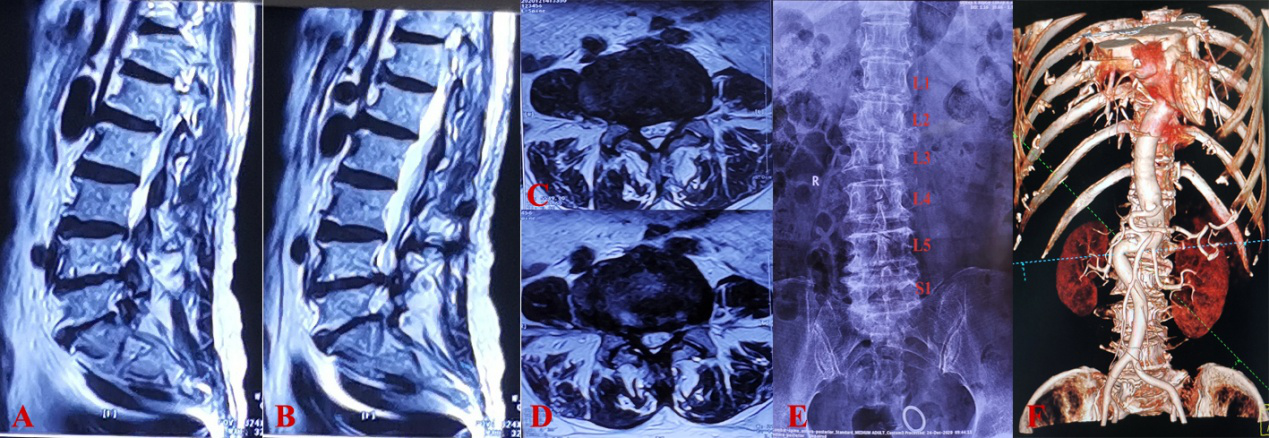

图3 术后复查腰椎CT、X线结果

A,术后腰椎正位片;B,术后腰椎侧位片;C,术后腰椎CT矢状位重建;D,术后腰椎CT冠状位重建

2020年12月30日,神经外科脊柱脊髓专业组在江玉泉教授的主持下,由姜政主任医师主刀,韩利章主治医师、张鑫住院医师为助手,泌尿外科赵海峰副主任医师提供技术指导,为该患者成功实施了腰5/骶1斜外侧椎间融合术。神经外科电生理监测小组陈思和吴倩倩医师为该患者的双下肢、膀胱及肛门实施全程电生理监测,为手术的安全进行保驾护航。术中充分发挥神经外科显微镜下操作的优势,对侧椎间隙清晰可见,终板处理彻底,减压充分。并置入13mm*55mm的巨大Cage,位置理想,椎间隙撑开明显(图2)。考虑到患者存在一定的骨质疏松,术中做了一期侧路双皮质钉棒固定。为了提高融合率,手术团队采用同种异体骨混合患者髂骨骨髓血进行融合,同时也避免了取自体髂骨带来的创伤。手术过程顺利,术中出血仅10ml左右。术后复查平片及CT示Cage及螺钉位置良好(见图3)。患者自诉症状较术前明显减轻,术后第三天患者即下地活动自如。患者恢复良好,于2021年1月5日出院。